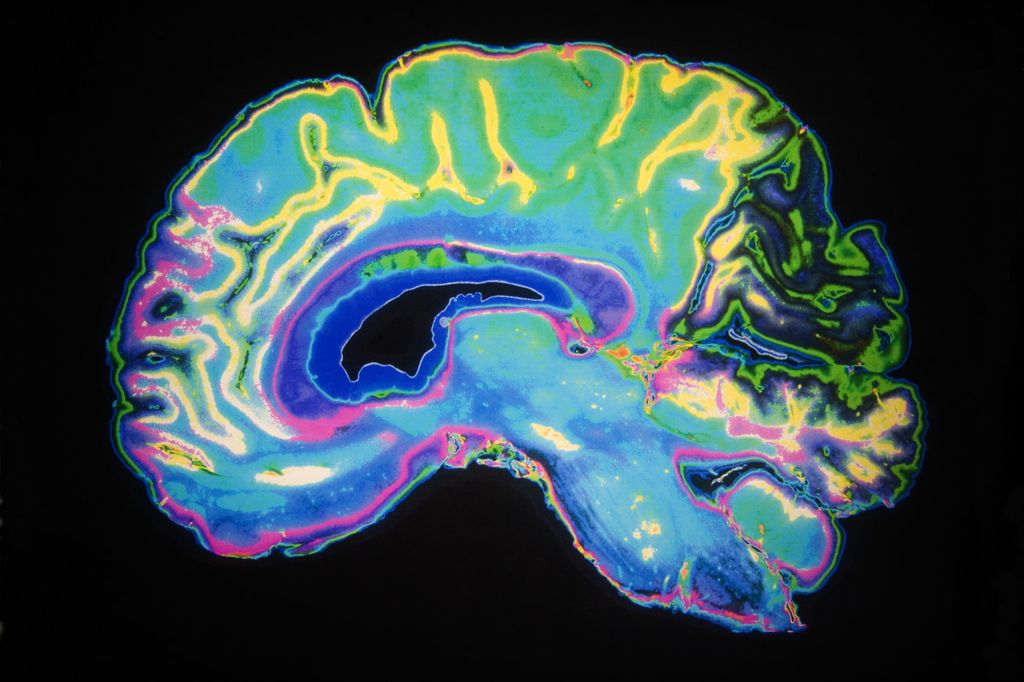

Bilim adamları, insan aklının duygularla nasıl etkileşim içine girdiğini anlamaya bir adım daha yaklaştı. Massachusetts Institute of Technology (MIT) bünyesinde çalışan bir ekip, beynin amigdala bölgelerinde olumlu ve olumsuz duygusal olayları işleyen iki nöral bağlantıyı ortaya çıkardı. Nöron gruplarını ışık hassasiyeti olan proteinlerle etiketleyen araştırmacılar, nöronların farklı durumlara karşılık vermek için paralel ancak aynı zamanda da karmaşık kanallar oluşturduğunu gözlemledi.

Bu bağlantılardan biri içinde olan nöronlardan bazılarının bir histen dolayı heyecan duyduğu, bazılarının ise çekingen kaldığı ve bu reaksiyonların belli bir kanaldaki birleşiminin deneyimlenen duyguyu belirleyebileceği ifade edildi.

Beynin duygu merkezi ile ilgili araştırma halen ilk aşamalarında. Araştırmacıların belirli nöron topluluklarını daha derinlemesine incelemesi ve nasıl bağlı olduklarını görmeleri gerekiyor. Buna ek olarak, daha geniş nöral ağların da açıkça tanımlanması da yapılacak işler listesinde yer alıyor. Araştırmaların başarıya ulaşması durumunda mental hastalıkların nasıl oluştuğunu ve geliştiğini anlamak mümkün hâle gelebilecek.

Kaygı ve depresyonun normalde mutluluk anında harekete geçmesi gereken nöronların işleyişini etkileyip etkilemediği de bu çalışmalar sonucunda ortaya çıkabilecek. Araştırmaların doğal reaksiyonları etkileyen problemlerin tedavisini de geliştirmesi amaçlanıyor.